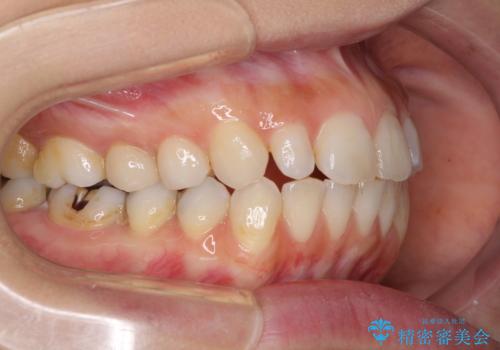

- 前歯のデコボコと矮小歯、更には痛みを感じる奥歯のむし歯を気にして来院された患者様です。

奥歯には根管治療が必要な歯があり、上顎側切歯は左右ともに矮小歯でした。

上下前歯のデコボコはワイヤーでもインビザラインでも対応可能でしたが、補綴治療が多く必要となることから、インビザラインでの矯正治療を行いながら、並行して補綴治療を行うこととしました。

まずは根管治療を行った上で矯正治療用の仮歯を装着し、矯正治療後半に補綴治療を並行して行うこととしました。